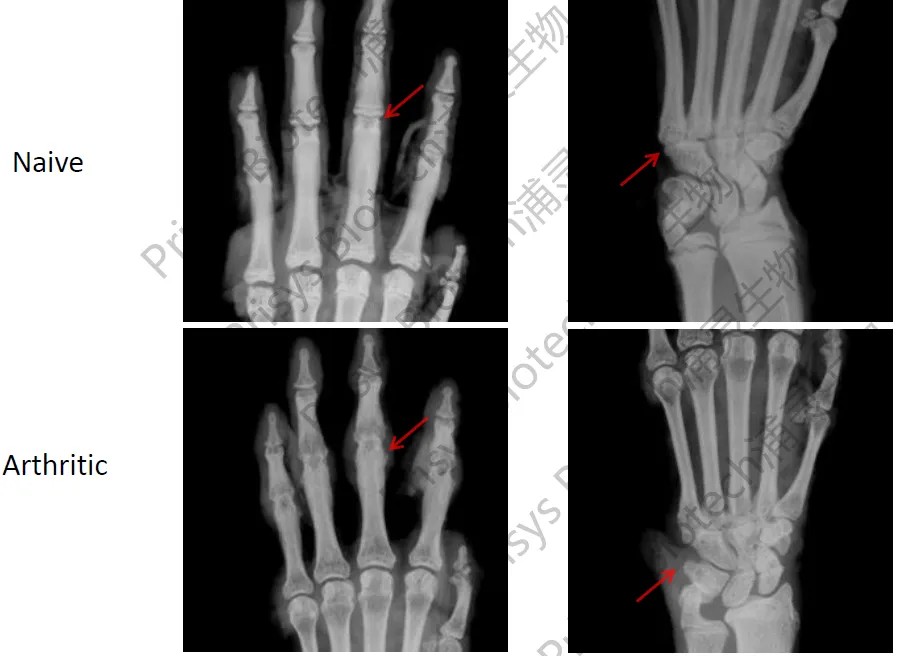

- 影像学评估:通过X光或CT成像直观观察骨密度丢失及关节变形。